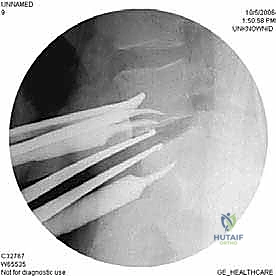

الخطوة 5: التثبيت (Fixation)

لضمان أقصى درجات الثبات والسماح للعظم بالاندماج بمرور الوقت، يتم تثبيت القفص باستخدام شريحة معدنية صغيرة ومسامير من التيتانيوم تُثبت في الأجسام الفقرية من الأمام. في بعض الحالات، قد يرى الدكتور هطيف ضرورة إضافة تثبيت خلفي بمسامير عبر الجلد (Percutaneous Pedicle Screws) لزيادة الدعم.

الخطوة 6: الإغلاق

بعد التأكد من وضعية الغرسات باستخدام الأشعة السينية داخل غرفة العمليات، يتم إعادة الأوعية الدموية والأعضاء الداخلية إلى وضعها الطبيعي، وتُغلق طبقات البطن بخيوط تجميلية.